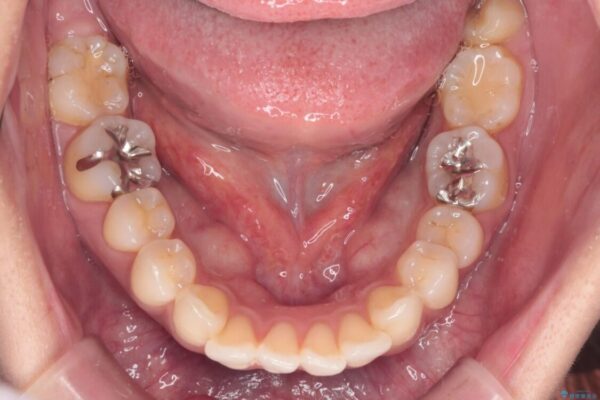

上の前歯の突出感を気にして来院された患者様です。

目立たない装置を希望とのことで、上顎左右第一小臼歯を抜歯し、インビザラインにて矯正治療を行うこととしました。

インビザラインにて抜歯矯正を行うと、高頻度で奥歯が咬み合わなくなります。

また、抜歯スペースに向けて奥歯が移動する際、必ず傾斜して移動するため、仕上がりの咬み合わせはワイヤー矯正と比べて明らかに劣ります。

治療前

• 上顎前歯の突出を軽減 インビザラインによる抜歯矯正 治療前画像